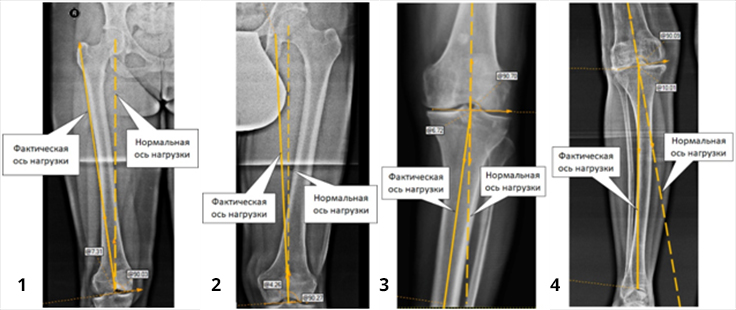

Деформации костей нижних конечностей подразделяют на варусные (1 и 3 фот) и вальгусные (2 и 4 фот). Эти деформации часто сочетаются с ротационными деформациями, когда ось сегмента конечности дополнительно поворачивается или вовнутрь, или наружу. Тогда говорят о сложных деформациях.

Кроме того, что деформации создают косметический дефект («Х-образные ноги», «ноги кавалериста»), они приводят к нарушению распределения нагрузочных сил в суставах, появлению болей в суставах и развитию артрозов. Своевременно выявленные и устраненные установочные деформации являются надежным способом предотвращения развития артрозов голеностопного, коленного и тазобедренного суставов.